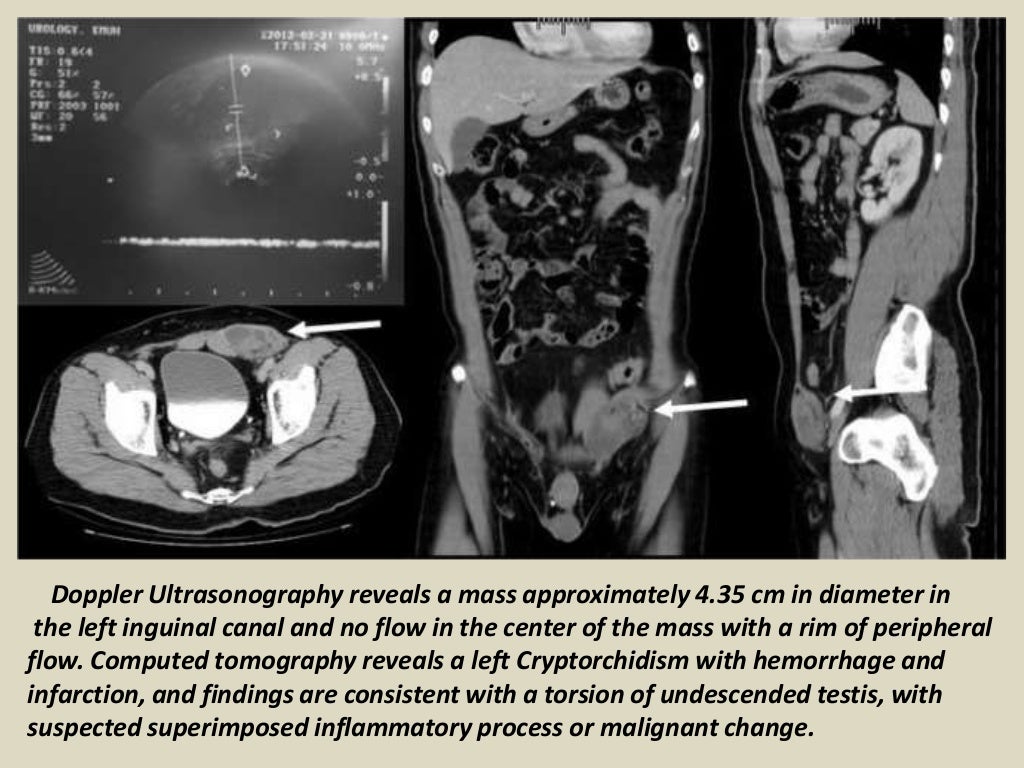

Presentation1, radiological imaging of undescended testis. What Is Undescended Testes In Tagalog These are the testes and. Male reproductive system diseases account for 14% of the burden of health in filipino men. And 10% of the time, it’s bilateral or affecting both testes. Instead, it’s in the groin or lower abdomen. Undescended testes is when one or both of the male testes have not passed down (descended) into the scrotal sac. Cryptorchidism. What Is Undescended Testes In Tagalog.